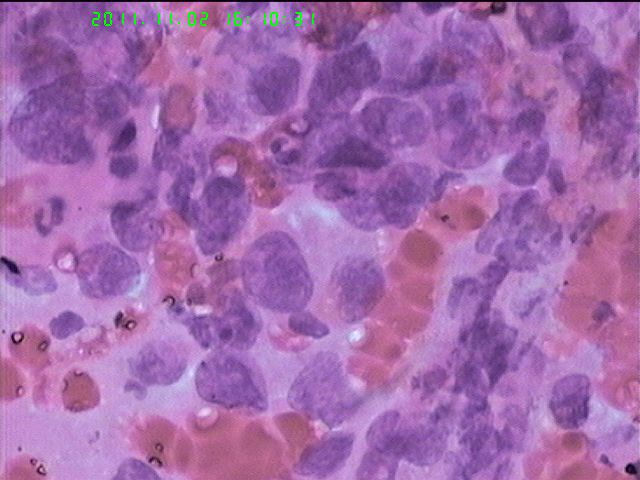

男65岁支气管刷片

我觉得不是大细胞神经内分泌癌。

你这例主要由于固定不及时,有些退变了,所以核看起来比较大。

胞浆比较丰富,而且均匀一致,所以我考虑腺癌。

非小细胞癌,我倾向与腺癌

楼主的制片都很漂亮,可以直接报鳞癌吗